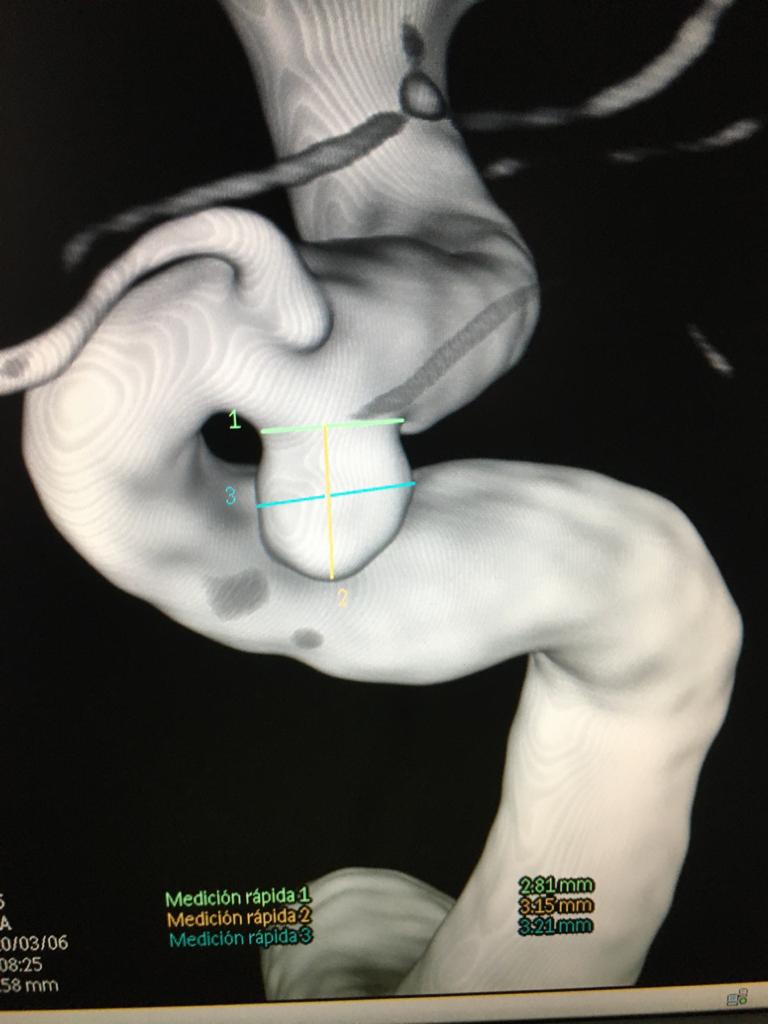

A frame image collection for your cases